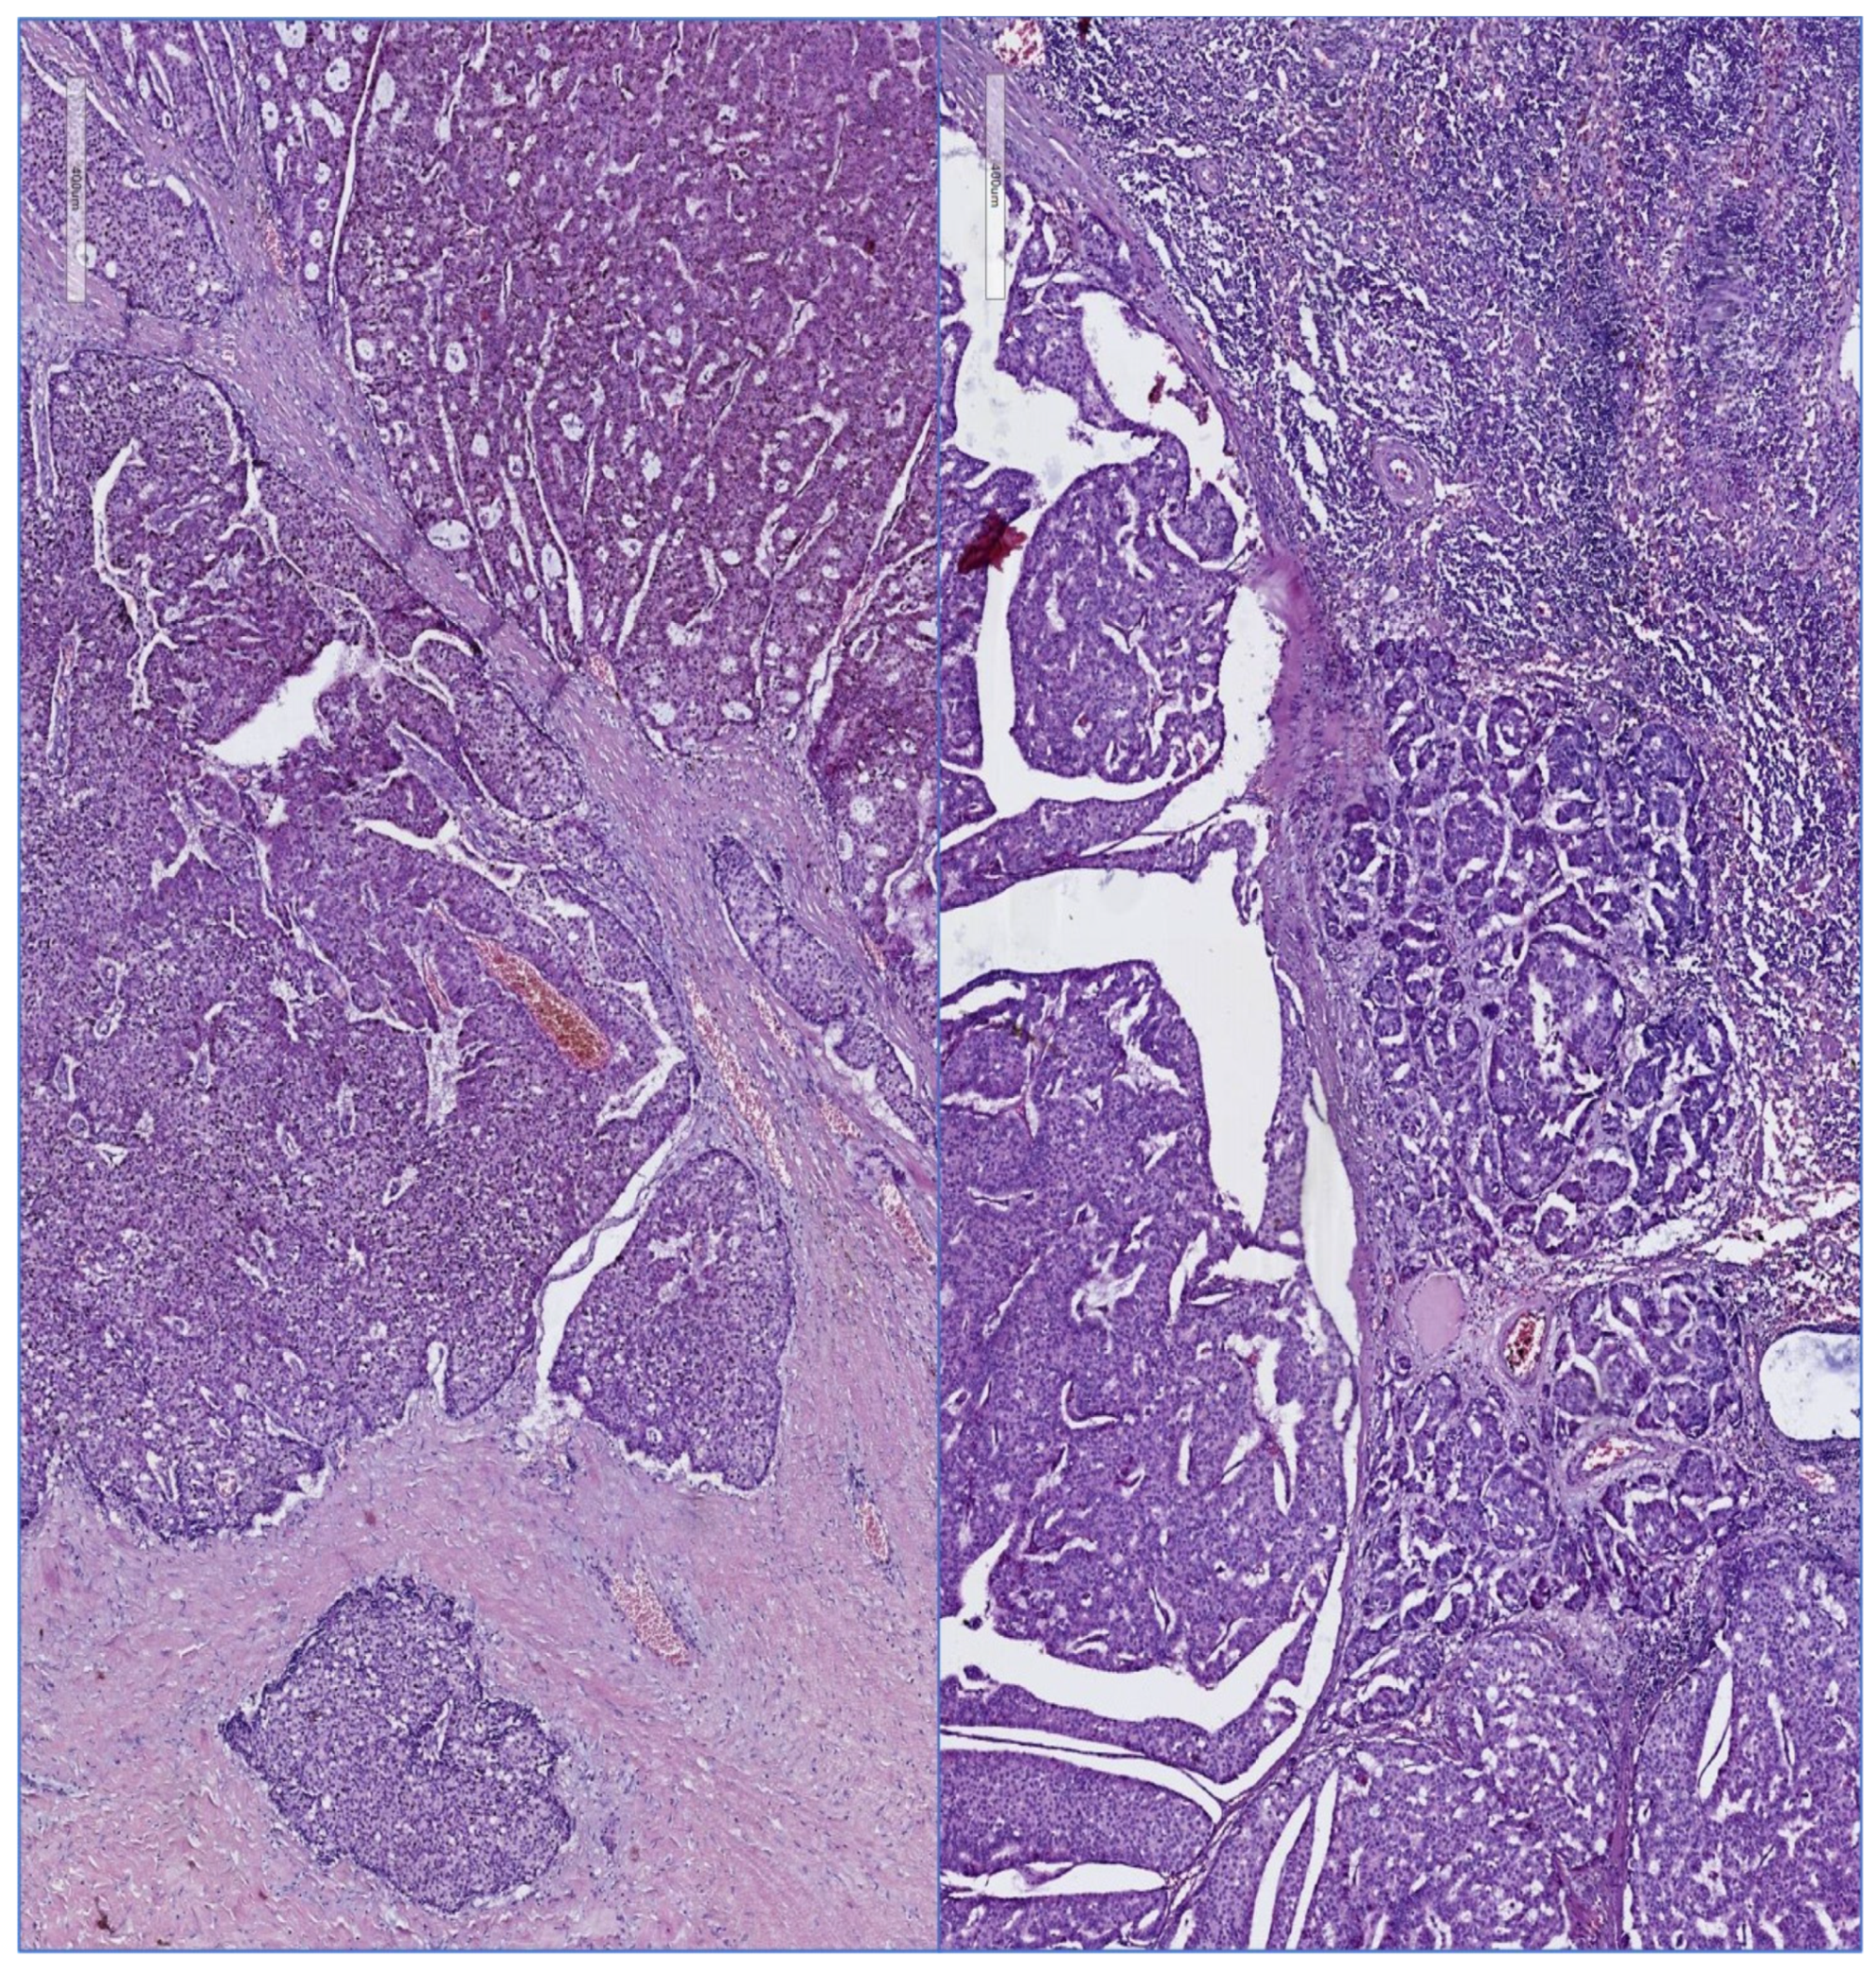

Figure 2 and Figure 3 illustrate different pathology caracteristics of breast cancer in male patients.

Figure 3.

Surgical resected specimen, same case: left panel: invasive mammary carcinoma, right panel: tumor invasion in an axillary lymph node, HE, 100×. Figure 2 and Figure 3 are presented courtesy of Dr. Mihai Ceausu, affiliated to the Pathology department of the “Prof. Dr. Al. Trestioreanu” Bucharest Oncology Institute and Associate Professor at the “Carol Davila” University of Medicine and Pharmacy, Bucharest, Romania.